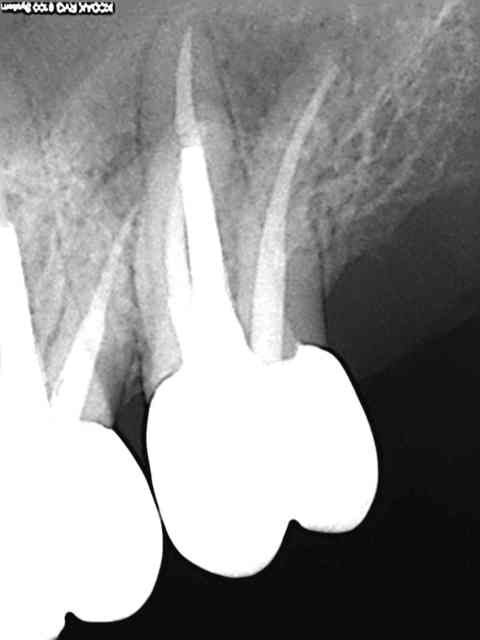

Cas pratique.4eme sur 27. Je me demande quel est le sagouin qui a fait l'endo. Oublié un mv2. Je lui ai taillé un short devant le patient. J'ai eu raison ?

R45 xndtrm - Eugenol

R39 iptohh - Eugenol

Ce praticien c'est moi. Endo faite en 2005. Ptain pas de digue en plus.))))) J'ai expliqué le pourquoi du comment ca a merdé, au patient. J'en ai bien chié pour le trouver ce mv2, meme tordu une sonde droite.

R48 hodugh - Eugenol